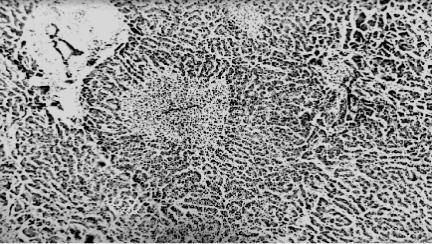

Впечени на фоне предшествовавшего в первом периоде ТБ болезни спазма артериол и шунтирования кровотока обнаруживают (рис. 41) моноцел- люлярные и групповые некрозы гепатоцитов (ишемическую гепатопатию).

Рис. 41. Микропрепарат печени при ишемиче- ской гепатопатии: мо- ноцеллюлярные и груп- повые некрозы гепато- цитов (окраска гематок- силином и эозином, × 100), рисунок С.А.

Повзуна